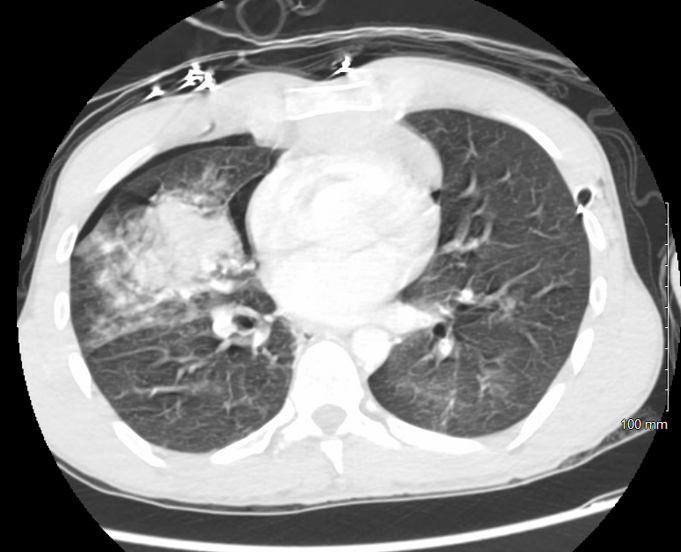

1) Pulmonary Contusion

Pulmonary contusion is a common consequence of blunt thoracic trauma, particularly in patients with multiple rib fractures or high-energy mechanisms such as motor vehicle collisions. Clinical signs may be delayed, developing over hours to days, and tachypnea, difficulty breathing, and hypoxemia are common symptoms. Contusions occur in roughly 30–75% of patients with substantial chest wall injury and are a key predictor of morbidity and mortality.

Radiographically, pulmonary contusions may be occult on initial chest X-ray, as findings often evolve over time and may not fully manifest until 24 to 72 hours after injury. CT imaging provides greater sensitivity and more accurately defines the extent of injury.

Management is supportive: supplemental oxygen, effective pain control, and pulmonary hygiene (e.g., chest physiotherapy) are foundational. Non-invasive ventilation is preferred when feasible, as intubation is typically reserved for more critically ill patients who require additional ventilatory support. Severe cases may progress to ARDS and require mechanical ventilation, with associated increases in ICU length of stay and pulmonary complications.

Saline fluid resuscitation should be judicious—overhydration may worsen pulmonary edema. In polytrauma patients requiring volume, intermittent use of diuretics may help mitigate overload and preserve oxygenation.